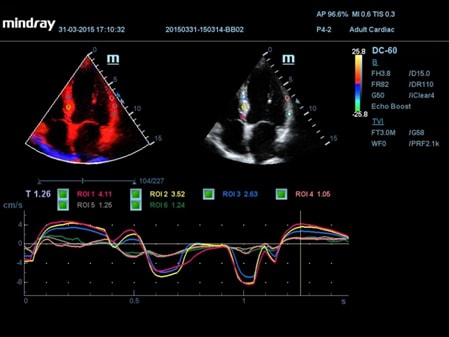

• TDI (Tissue Doppler imaging, including TDI Color, Power, PW and M mode) - пакет тканевой доплерографии.

• TDI Quantification Analysis Software - количественный анализ тканевого доплера.

• TDI (Tissue Doppler imaging, including TDI Color, Power, PW and M mode) – пакет тканевой допплерографии, включая цветное картирование, импульсный тканевой допплер, энергетический тканевой допплер и тканевой М-режим

• TDI Quantification Analysis Software - количественный анализ тканевого допплера (необходима опция TDI)